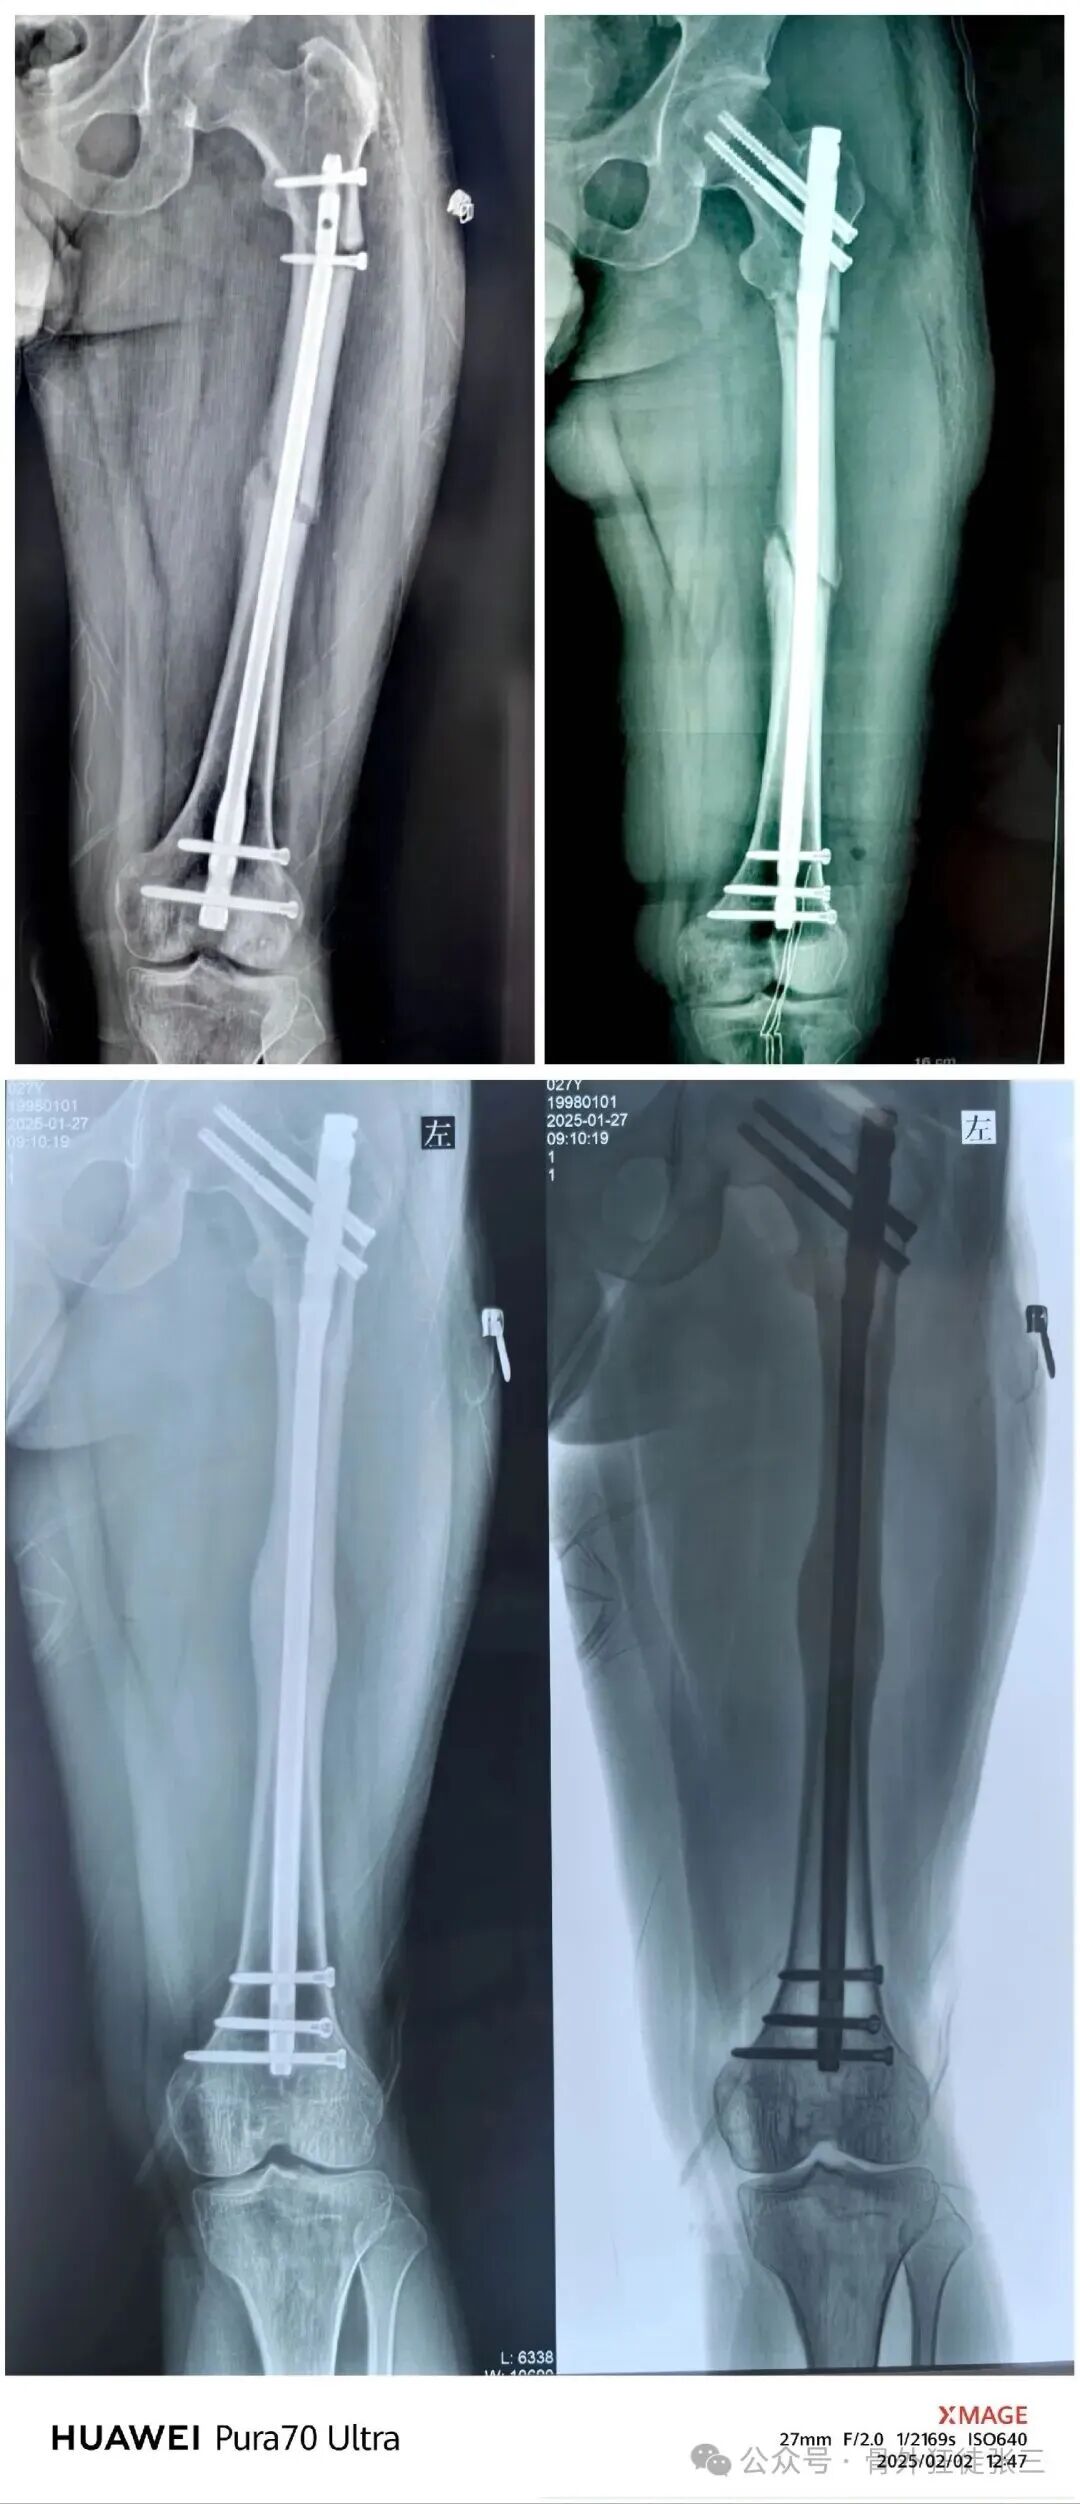

再来分析下失败原因

1,能顺行不逆行,选择了逆行

2,能闭合不切开,选择了切开

当然再骨折的原因

大概率是近端锁钉锁不准

打孔次数过多的原因

但是青壮年逆行髓内钉

再次受到暴力

仍旧避免不了

转子下,股骨颈骨折的风险

我们给予翻修

1,顺行髓内钉,头颈模式

2,全长保护,

3,最粗,够长

4,扩髓约等于植骨

术后5个月完全愈合

这样全长保护

转子下,股骨颈或者股骨远端再骨折的概率

是不是非常小

几乎不会再出现?

这个患者术后14个月取了髓内钉

术后已经随访了两年